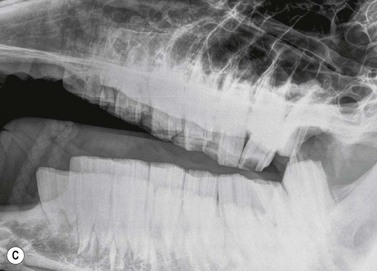

Fig. 13.35 Oligodontia. The pony in (A) has anodontia of 308, 408 and 108, although the deciduous remnant (‘cap’) of one lower 08 is still present.

Radiograph courtesy of P.M. Dixon.

image

The pony in (B) has only 5 teeth in both mandibular rows, with large overgrowths of the upper 10s and 11s and secondary diastemata formation between the upper 09s and 10s.